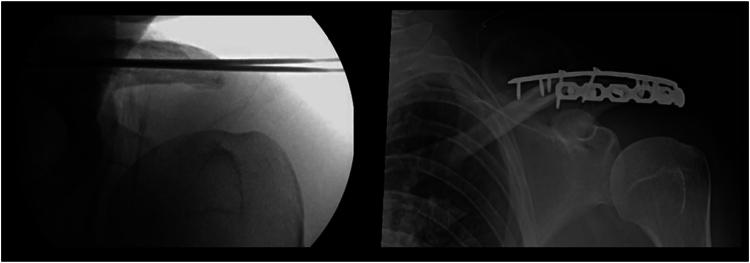

Acromion fracture associated with traumatic first time anterior shoulder dislocation: a case report.

JSES Rev Rep Tech. 2023 Dec 16;4(2):284-290. doi: 10.1016/j.xrrt.2023.11.002. eCollection 2024 May.

Acromion fracture associated with traumatic first time anterior shoulder dislocation: a case report.首次创伤性肩关节前脱位伴肩峰骨折:一例报告